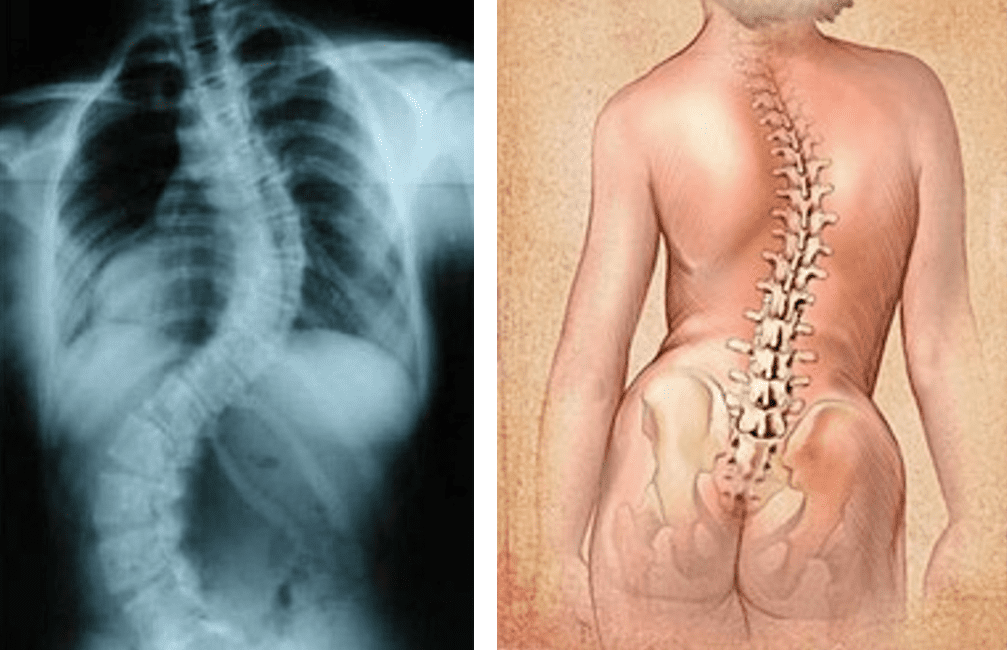

- skolioza- trójpłaszczyznowa deformacja kręgosłupa

Skolioza- trójpłaszczyznowa deformacja kręgosłupa

- skolioza pow. 45st.( Cobba) Skrzywienia statystycznie pogarsza się o ok. 1 st. rocznie

- w ciąży o 5st. rocznie

- planowanie rodziny

- inne deformacje n. ruchu także pogłebiają się pod wpływem relaksyny – rola ruchu

i profilaktyki.

- w ciąży ( pod koniec) ból może się nasilać – rola mięśni